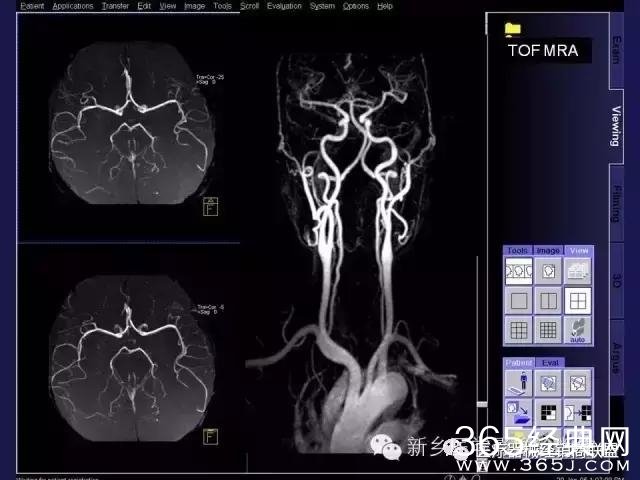

CT、MRI很难?NO,今日我们一起来学习一下如何读CT、MRI!

内行看门道:

整整90张图